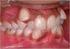

3 KELAINAN DENTOFASIAL = DENTOFACIAL ANOMALI 1. Besar gigi dipengaruhi oleh ras dan keturunan 2. Bentuk gigi dipengaruhi : Ras : Gigi incisivus pertama orang Afrika permukaan lingualnya lebih halus. Keturunan: Besar setelah erupsi tidak berubah 3. Jumlah gigi : yang sering mengalami agenese adalah : M3, 12, P2, I1, P1 4. Posisi gigi : Inklisasi aksial, tonjol gigi yang rendah; tonjol gigi yang lebih tinggi, rotasi, hal ini akan mempengaruhi bentuk lengkung gigi, aktivitas TMJ, fungsi otot perioral atau sekitar mulut. Faktor-faktor yang dapat menyebabkan maloklusi : 1. Keturunan 2. Lingkungan 3. Fungsional Maloklusi adalah hal yang menyimpang dari bentuk standar yang diterima sebagai bentuk normal. GOLONGAN MALOKLUSI : 1. Dental displasia 2. Skeleto Dental displasia 3. Skeletal displasia 1. Dental displasia : malokiusi bersifat dental, satu gigi atau lebih dalam satu atau dua rahang dalam hubungan abnormal satu dengan lain. Hubungan rahang atas dan rahang bawah normal Keseimbangan muka dan fungsi normal Perkembangan muka dan pola skeletal baik Macam-macam kelainan : Universitas Gadjah Mada 3

4 Misalnya : kurang tempatnya gigi dalam lengkung, oleh karena prematur loss, tambalan kurang baik, ukuran gigi lebih besr, sehingga dapat terjadi keadaan linguiversi, labioversi dan sebagainya. 2. Skeleto Dental displasia Tidak hanya giginya yang abnormal, tetapi dapat terjadi keadaan yang tidak normal pada hubungan rahang atas terhadap rahang bawah, hubungan rahang terhadap kranium, fungsi otot dapat normal atau tidak tergantung macam kelainan dan derajat keparahan kelainan tersebut. 3. Skeletal Displasia Dalam kelainan skeletal displasia terdapat hubungan yang tidak normal pada : a. Hubungan anteroposterior rahang atas dan rahang bawah terhadap basis kranium. b. Hubungan rahang atas dan rahang bawah c. Posisi gigi dalam lengkung gigi normal KLASIFIKASI MALOKLUSI Tujuan : Untuk menggolongkan maloklusi ke dalam kelompok-kelompok dimana tiap-tiap kelompok memiliki sifat-sifat khas yang mudah ditandai dan mempunyai variasi yang pokok. Maksud Memudahkan analisa etiologi, cara perawatan dan prognosa tiap-tiap kelompok. KLASIFIKASI ANGLE Dasar : Hubungan mesiodistal yang normal antara gigi-geligi rahang atas dan rahang bawah. Sebagai kunci oklusi digunakan gigi M1 atas. Dasar pemilihan 1. Merupakan gigi terbesar 2. Merupakan gigi permanen yang tumbuh dalam urutan pertama 3. Tidak mengganti gigi desidui 4. Bila pergeseran gigi M1 maka akan diikuti oleh pergeseran poros gigi lainnya. 5. Jarang mengalami anomali 1. Kelas I Angle = Neutro Oklusi Universitas Gadjah Mada 4